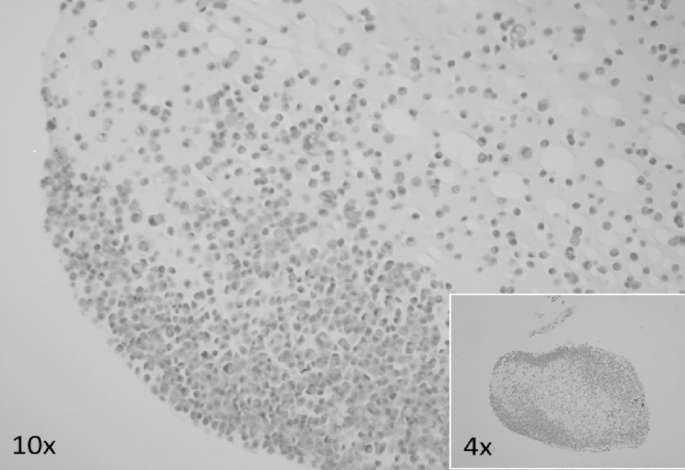

First, the collected cells were suspended in Phosphate Buffered Saline (PBS), collected by centrifugation, mixed with alginate solution (catalog number: 2023; 50K0180), and immersed in a calcium chloride solution (catalog number: 2023; 21097-250G) to form conglomerates, fixed using a 10% buffered formalin solution. After fixation, the conglomerates were processed in a tissue processor and embedded in paraffin [Figure 2a]. For 3D culture, alginate beads were formed by adding 1% alginate solution to adipose-derived stem cells. The cell blocks were then sectioned into 4 μm-thick slices on a hand-held rotary microtome, applied to basal slides, and stained with H&E [Figure 2b]. Finally, the material was sliced into 3 μm-thick sections, placed on Superfrost Plus basal slides with increased adhesion, and underwent automated immunohistochemical staining [Figure 2c]. In this experimental setting, fixation with 10% buffered formalin was performed after the formation of alginate conglomerates. This sequence differs from the workflow used for clinical cytological specimens (Sect. 2.1.1), where fixation typically precedes alginate encapsulation due to the need for immediate preservation and unknown cellularity. In controlled laboratory conditions with predefined cell content, post-encapsulation fixation allows for optimal bead formation and structural preservation.

Steps for alginate-encapsulated cell block preparation for in vivo studies on the example of IHG-MUC360 mucoepidermoid carcinoma cell line. (A) The cell suspension underwent centrifugation, and an alginate solution and calcium chloride solution were subsequently introduced. The resulting conglomerates were fixed using a 10% buffered formalin solution and Duboscq fluid. Then, they were processed through a routine diagnostic procedure in a tissue processor and embedded to create paraffin blocks. (B) The cellular material embedded in paraffin was sectioned into 4 μm-thick slices using a hand-held rotary microtome. These paraffin sections were applied to basal slides, and automated hematoxylin-eosin staining was performed. (C) The test material was sliced into 3 μm-thick sections using a hand-held rotary microtome and placed on Superfrost Plus basal slides with increased adhesion. An automated immunohistochemical staining procedure was conducted. The cell line showed positive expression for CK, EMA, Ki67, P53, p63, and GOPC while also not expressing Bcl-2 and CK20.